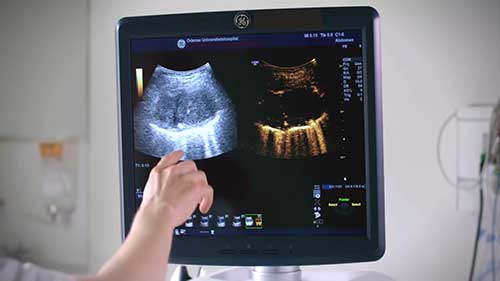

三种医用超声诊断仪

学习血管内超声仪(IVUS)、对比增强超声仪(CEUS),以及针电极超声仪这三种医用超声诊断仪的基本知识。

肌肉骨骼超声诊断

肌肉骨骼超声诊断是使用高频超声对肌肉、骨骼系统等方面疾病进行检查。短片演示了用超声诊断仪进行肌肉骨骼超声检查。

更换超声诊断仪的扫描模块

超声波诊断仪由仪器计算机、控制台、扫描模块等部件组成。短片演示了更换扫描模块的过程。